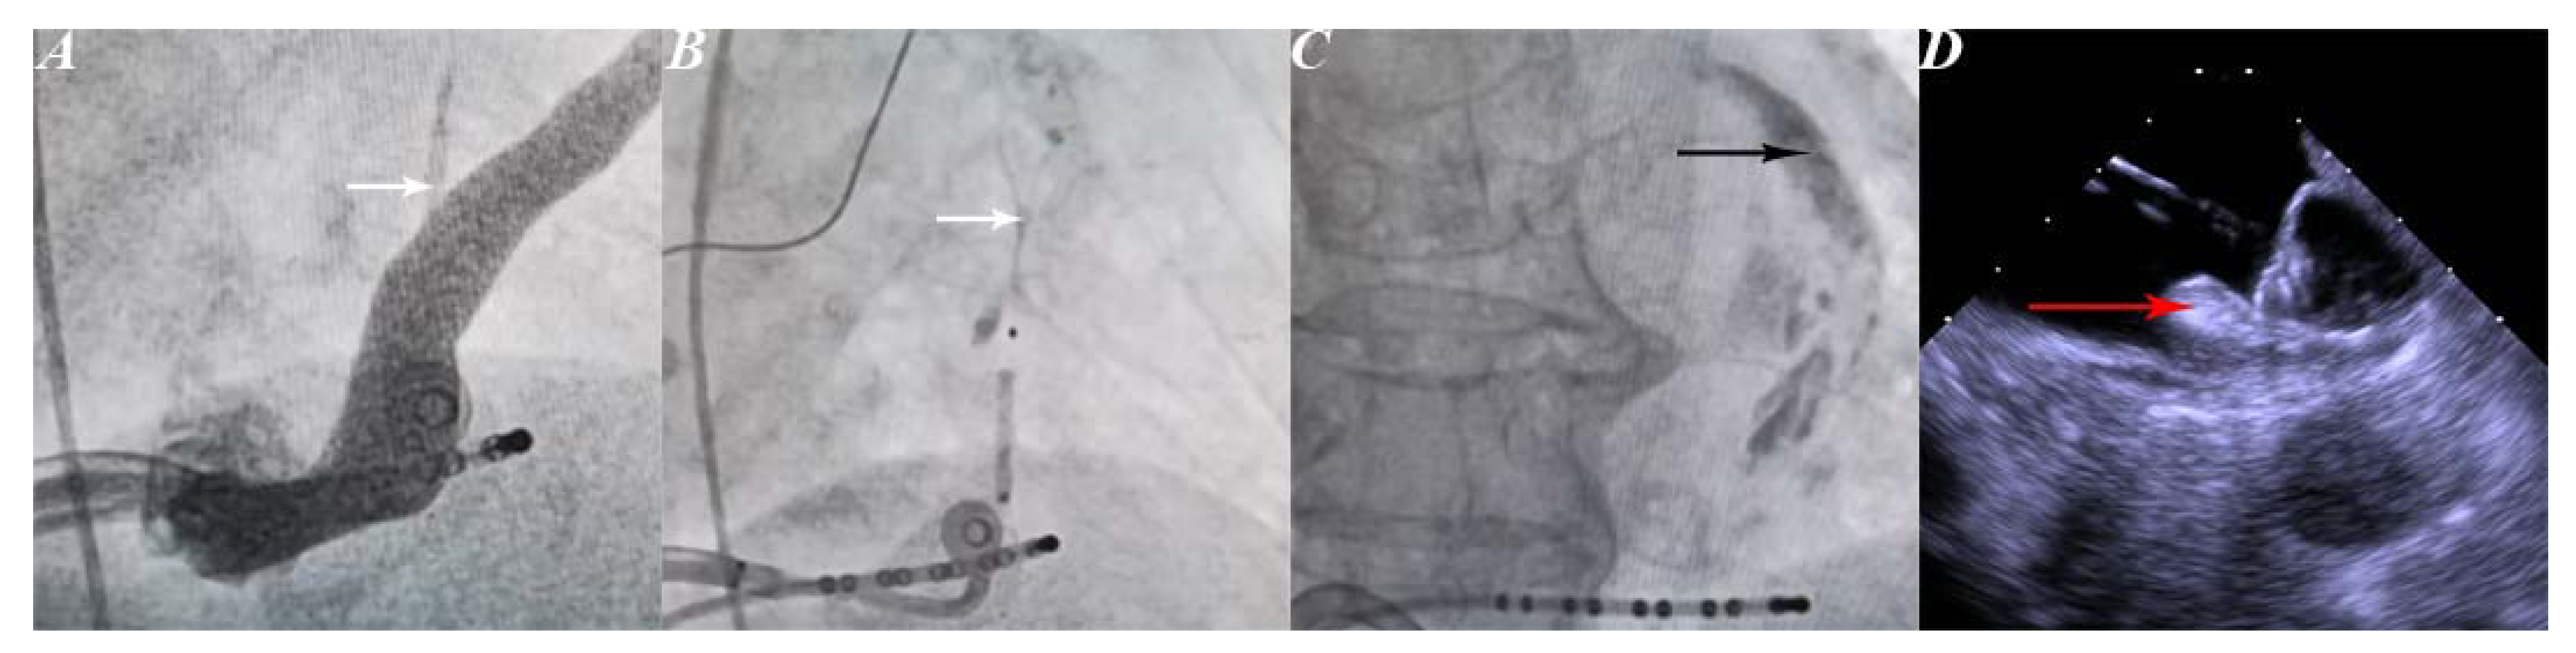

2.2.1. Ethanol Infusion in the Vein of Marshall

2.2.2. Left Atrial Appendage Occlusion